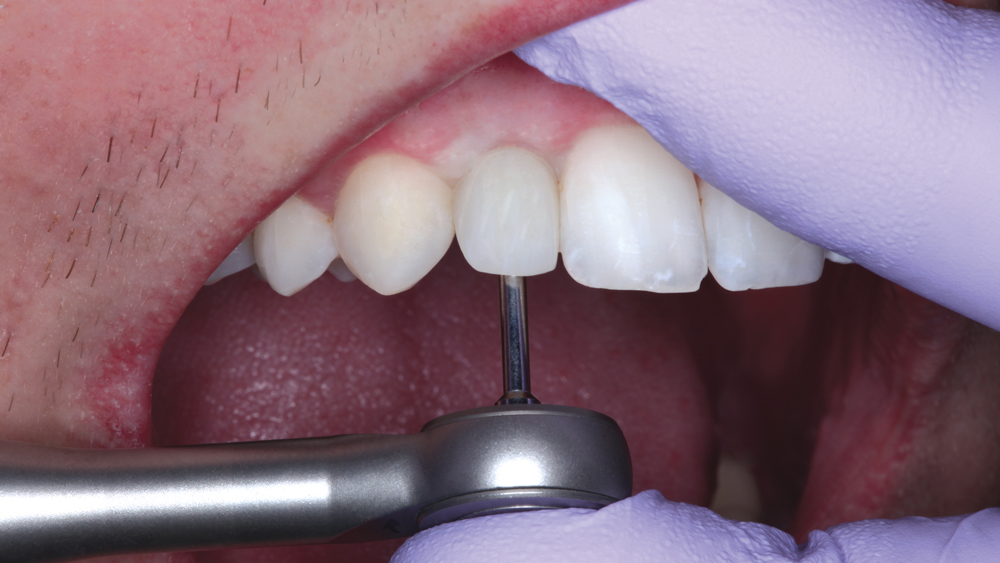

The following case illustrates the efficient, straightforward clinical workflow for placing Hahn Tapered Implants via guided surgery. A digital treatment plan is developed in which a 3.5 mm implant is positioned to support the ideal prosthetic outcome. An immediate provisional crown is designed in concert with the surgical guide and delivered at the time of surgery, helping to produce a predictable, highly esthetic restoration for a demanding case in the smile zone.